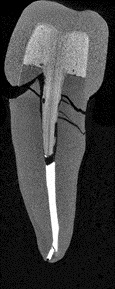

While none of the everX Posterior specimens had a non-restorable failure mode four specimens (26.67%) of the prefabricated FRC post specimens had a non-restorable deep root fracture (Image 2 and 3).